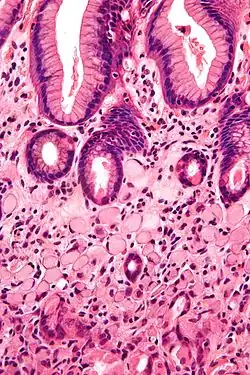

| A signet ring cell, as seen in a case of colon adenocarcinoma with mucinous features, showing a tumor cell with a vacuole of mucin. H&E stain. | |

SRCCs are named due to their resemblance to signet rings, which result from the formation of large vacuoles full of mucin that displaces the nucleus to the cell's periphery.[16]